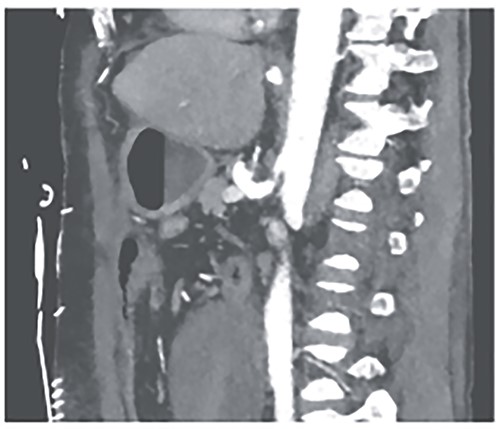

A 52-year-old otherwise healthy patient was admitted to the emergency room of our hospital with an acute abdomen and hemodynamic instability. The computed tomography (CT) angiography revealed an active, most likely aneurysmal bleeding of the pancreaticoduodenal artery with venous pooling, along with a large retroperitoneal hematoma measuring ~2000 ml in volume (Fig. 1). Due to hemodynamic instability and the unavailability of interventionalists, the decision for emergent exploratory laparotomy was made. Intraoperatively was a ballooned and hemorrhagic retroperitoneum with incipient perforation of the mesenteric root observed. To gain exposure, an extended Kocher maneuver according to Cattell–Braasch was performed, necessitating a rightsided hemicolectomy. The bleeding was managed by ligating the pancreaticoduodenal artery. An Easy-Flow drainage was placed, and a split stoma was created. Intraoperatively, due to an estimated blood loss of over 4 L, transfusion therapy was administered following a massive transfusion protocol, along with extensive coagulation correction.

CTA showing an active bleeding likely from the pancreaticocuodenal artery with venous pooling and a large retroperitoneal hematoma.